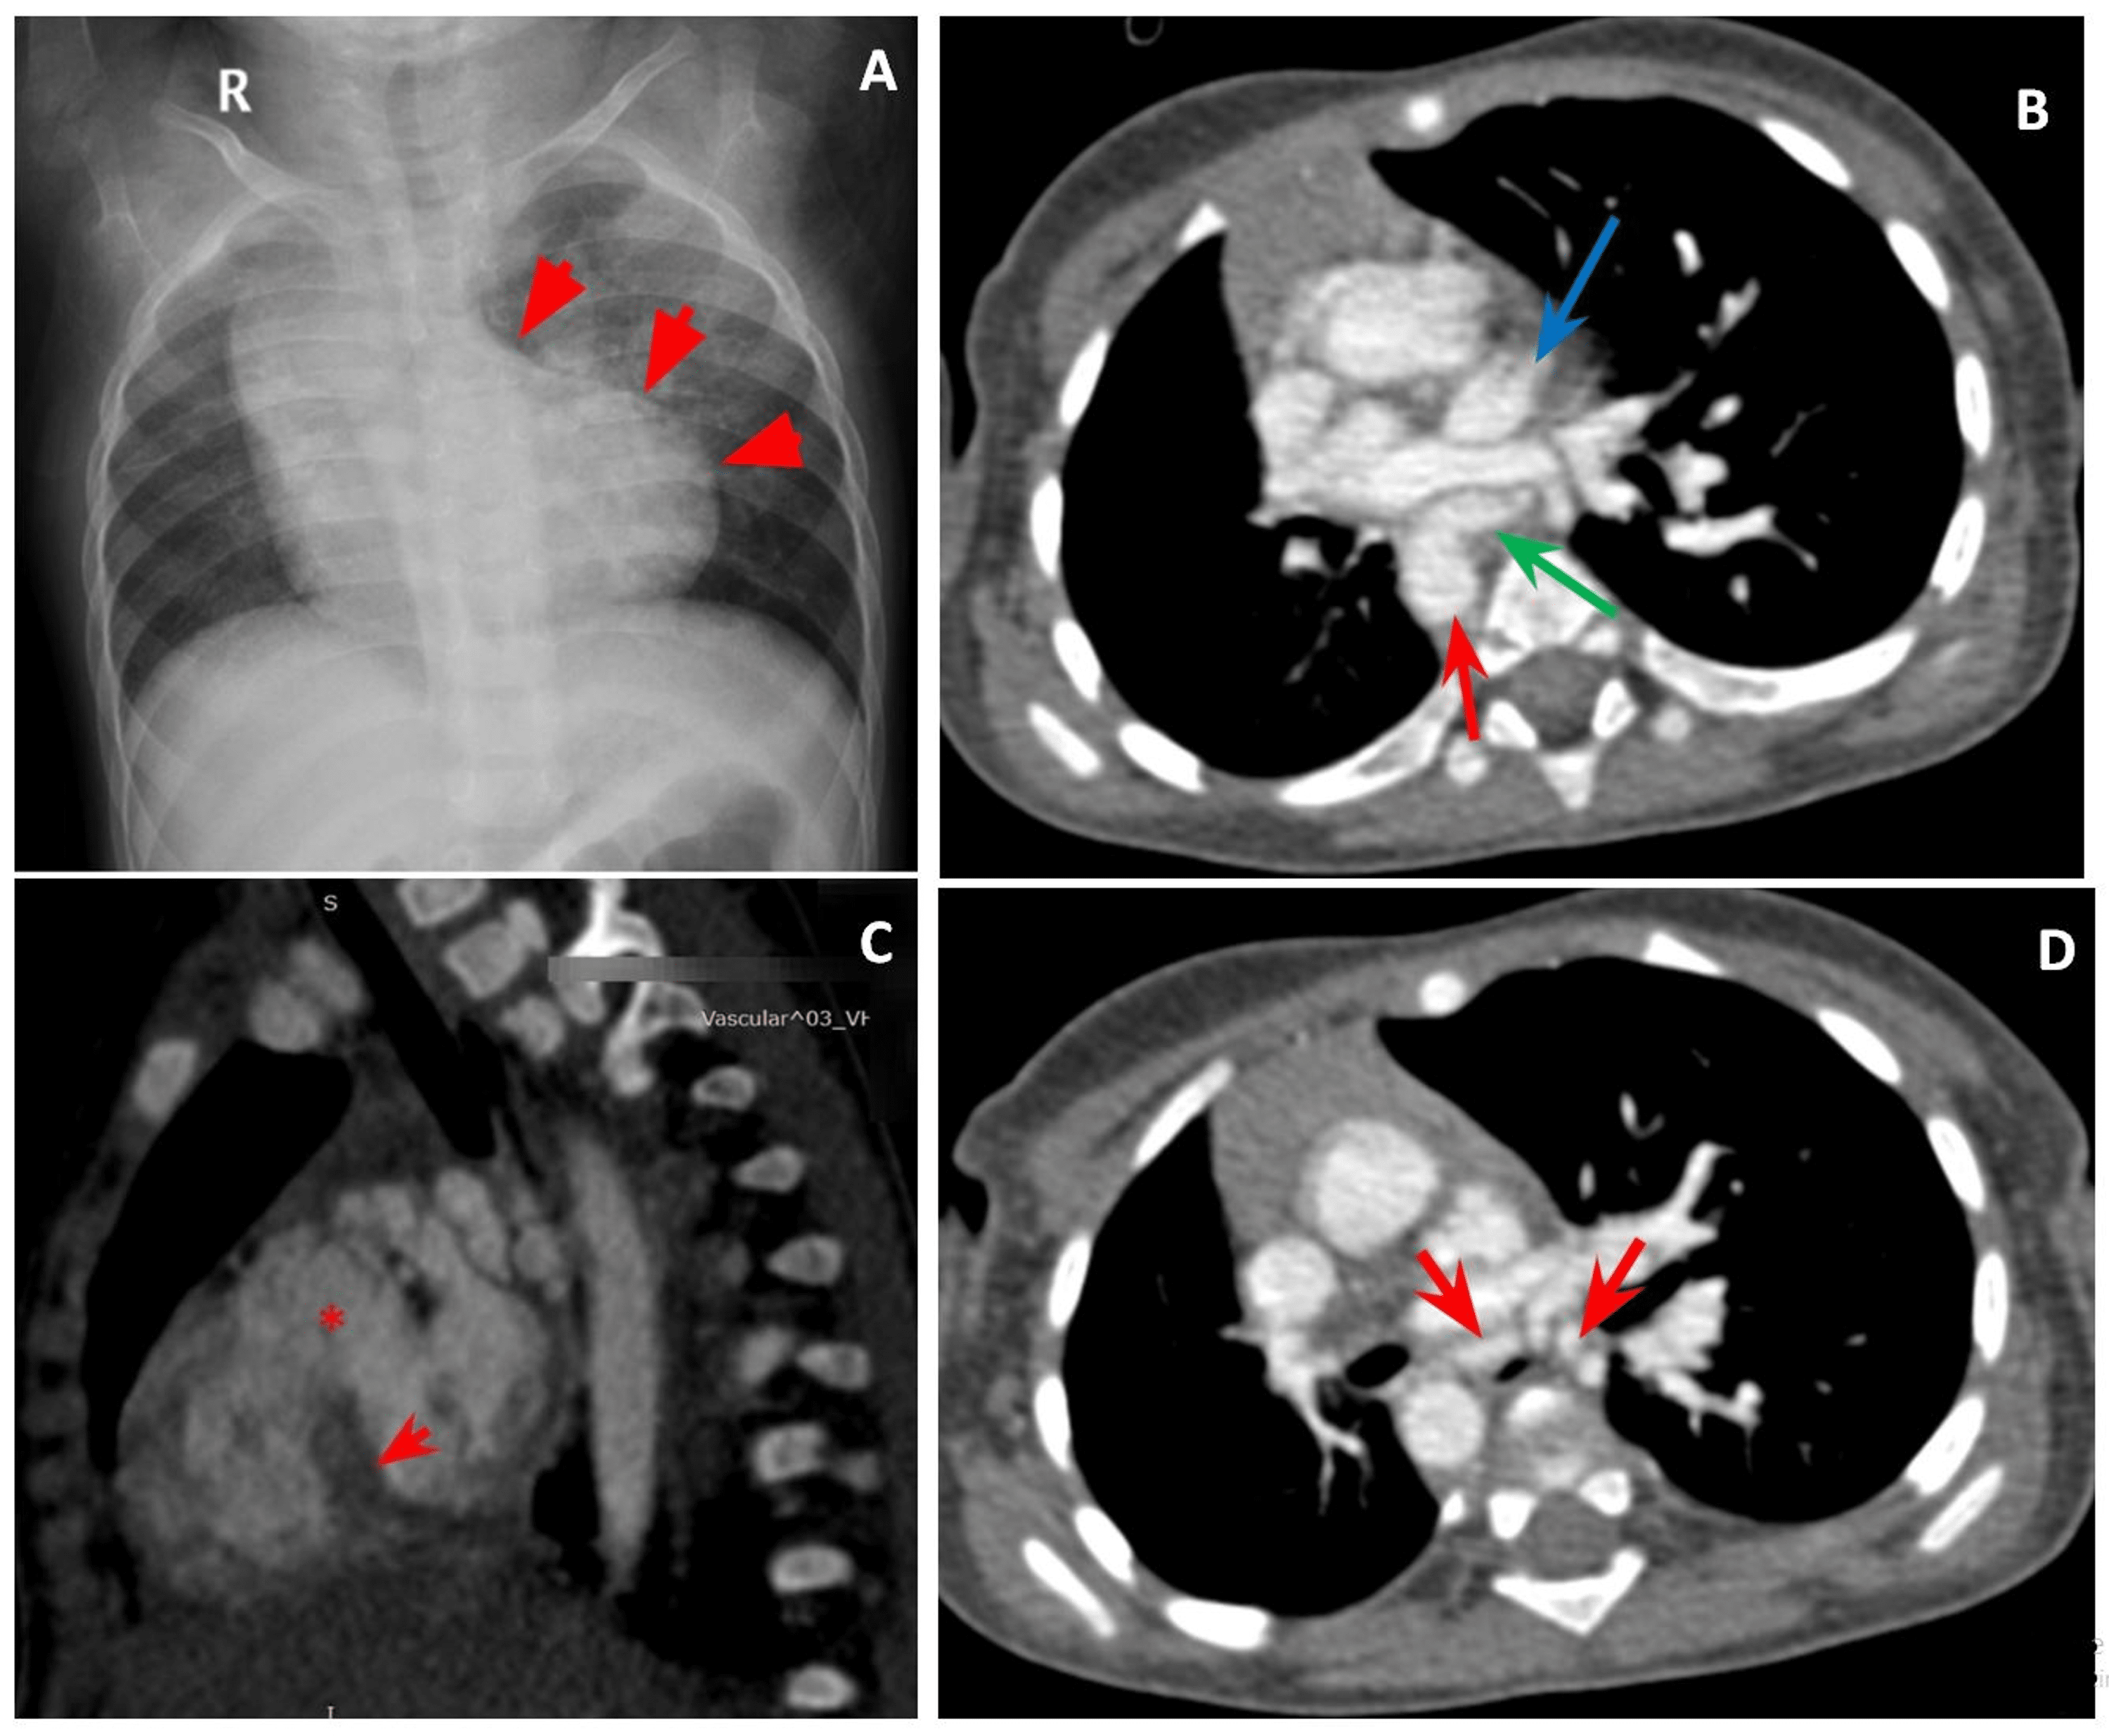

CT image of occluded right pulmonary artery and aortic dissection Occluded Pulmonary Artery Measurements of pulmonary artery occlusion pressure (paop) should be performed by slow. Ct findings of a chronic pe include (i) complete occlusion of a vessel; The selective reverse pulmonary wedge pulmonary vein angiogram can be useful to definitively delineate the anatomy of the. Pulmonary vascular disease is the medical term for disease affecting the blood vessels leading to or from. Occluded Pulmonary Artery.

CT image of occluded right pulmonary artery and aortic dissection Occluded Pulmonary Artery Pulmonary vascular disease is the medical term for disease affecting the blood vessels leading to or from the lungs. The selective reverse pulmonary wedge pulmonary vein angiogram can be useful to definitively delineate the anatomy of the. When a pulmonary artery is occluded, the pressure in bronchial arteries increases to perfuse pulmonary capillaries. Measurements of pulmonary artery occlusion pressure (paop). Occluded Pulmonary Artery.